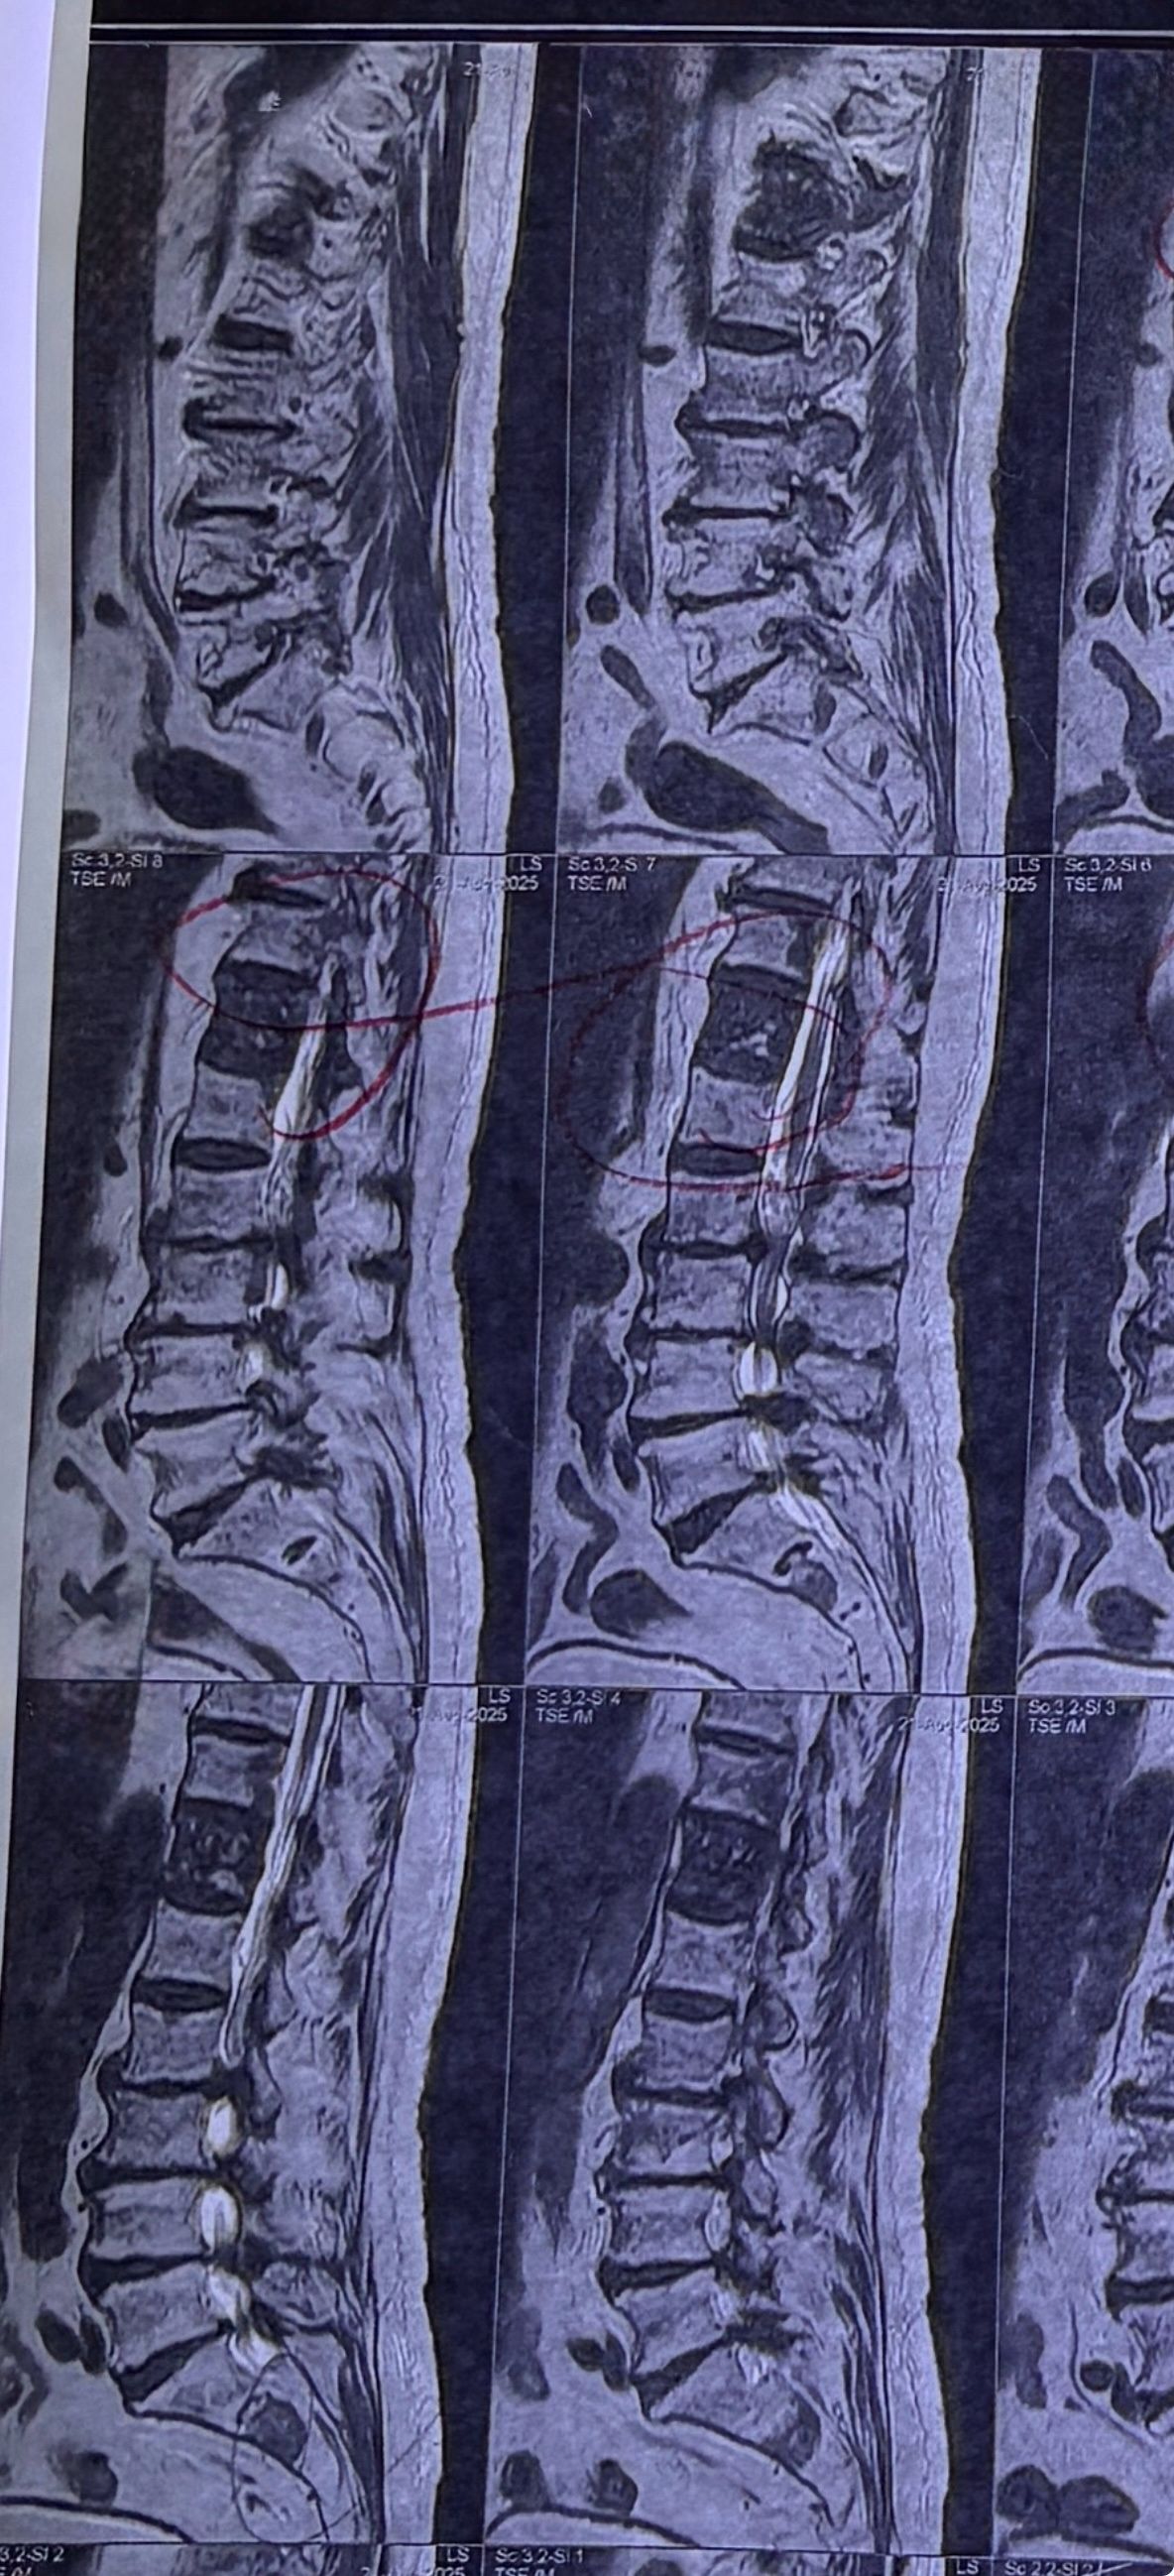

40 yrs old male patient presented to my office who had severe R gluteal pain and radicular pain along R L5-S1 now pain has reduced by 80% in his motor exam had R big toe L5 motor reduced to 4+\5 and R S1 DTR was 0 while L S1DTR was 1+

We did EMG/NCV which showed Mod- sever R L5 S1 irritation without any active axonal loss

I had to decide to refer him for surgery or not patient didn’t have any treatment meanwhile

I ordered new L/S mri

I posted his new mri and old mr

Which was 20 days ago and have posted all below

The first 12 mris had been done 20 days ago

After those first 12 MRIs i have posted new MRIs which were done yesterday

After seeing his new mri and emg/ncv and getting sure his neurological deficit is not active and progressing i told patient he doesn’t need surgery at this time and released him with some advices and exercises

Keep in mind when patient is 80-90 percent pain free and stable i would never give treatment to them just give exercises and follow up their condition